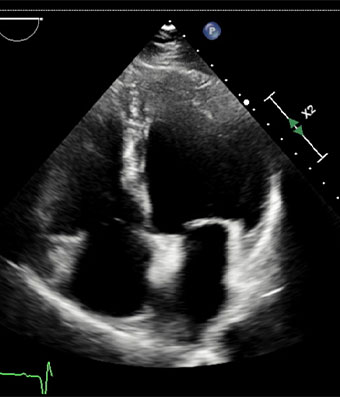

Ecocardiografía

El ecocardiograma o ecocardiografía utiliza ondas sonoras de alta frecuencia para obtener imágenes del corazón en vivo y que son proyectadas en una pantalla. Este auxiliar diagnóstico aporta información en 30 a 60 minutos de la forma, tamaño, función y movimiento del corazón así como de sus estructuras internas, como por ejemplo las válvulas cardiacas. Este estudio es seguro en pacientes adultos, en pacientes pediátricos (ecocardiograma pediátrico) o incluso en mujeres embazadas para estudiar el desarrollo del corazón del bebé en la cavidad uterina (ecocardiografía fetal).

Las imágenes ecocardiografías del corazón pueden ser obtenidas en diferentes modos (unidimensional, bidimensional o tridimensional, Doppler, Doppler color), utilizando una sonda externa (ecocardiograma transtorácico) o una sonda interna (ecocardiograma transesofágico) y puede ser adquirido en reposo, en estrés con esfuerzo físico o con el uso de medicamentos (estrés con dobutamina), dependiendo del diagnóstico y de la indicación de tú médico.